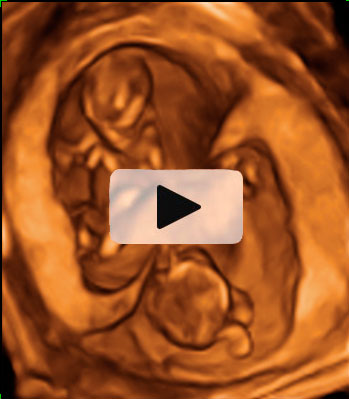

Ecografía 4D de la semana 12: Feto moviéndose de perfil

La ecografía 4D muestra al bebé moviéndose a sus anchas en el útero materno. Este plano de perfil muestra brazos, piernas y cordón umbilical en movimiento constante, lo que es es signo de vitalidad fetal. Las estructuras básicas de un feto de 12 semanas de gestación se parecen mucho a las de un bebé recién nacido; es ya todo un niño, aunque le falten unos seis meses aproximadamente para ver la luz.

Ecografía 4D: feto de 12 semanas moviéndose de perfil